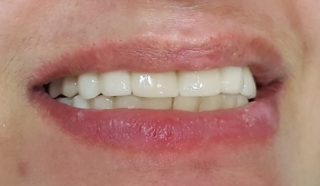

“The QDC Dental Implants”

look and feel like your very natural teeth designed to be fixed for lifetime.